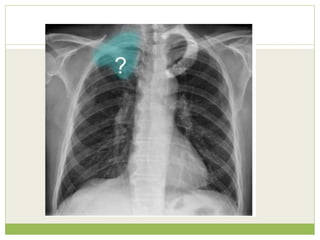

Findings

Left apical shadowing

Raised left hemidiaphragm

Increased extra-thoracic

soft tissue density (*) with

displacement of the

scapula on the left

(arrowheads) - compare

with right